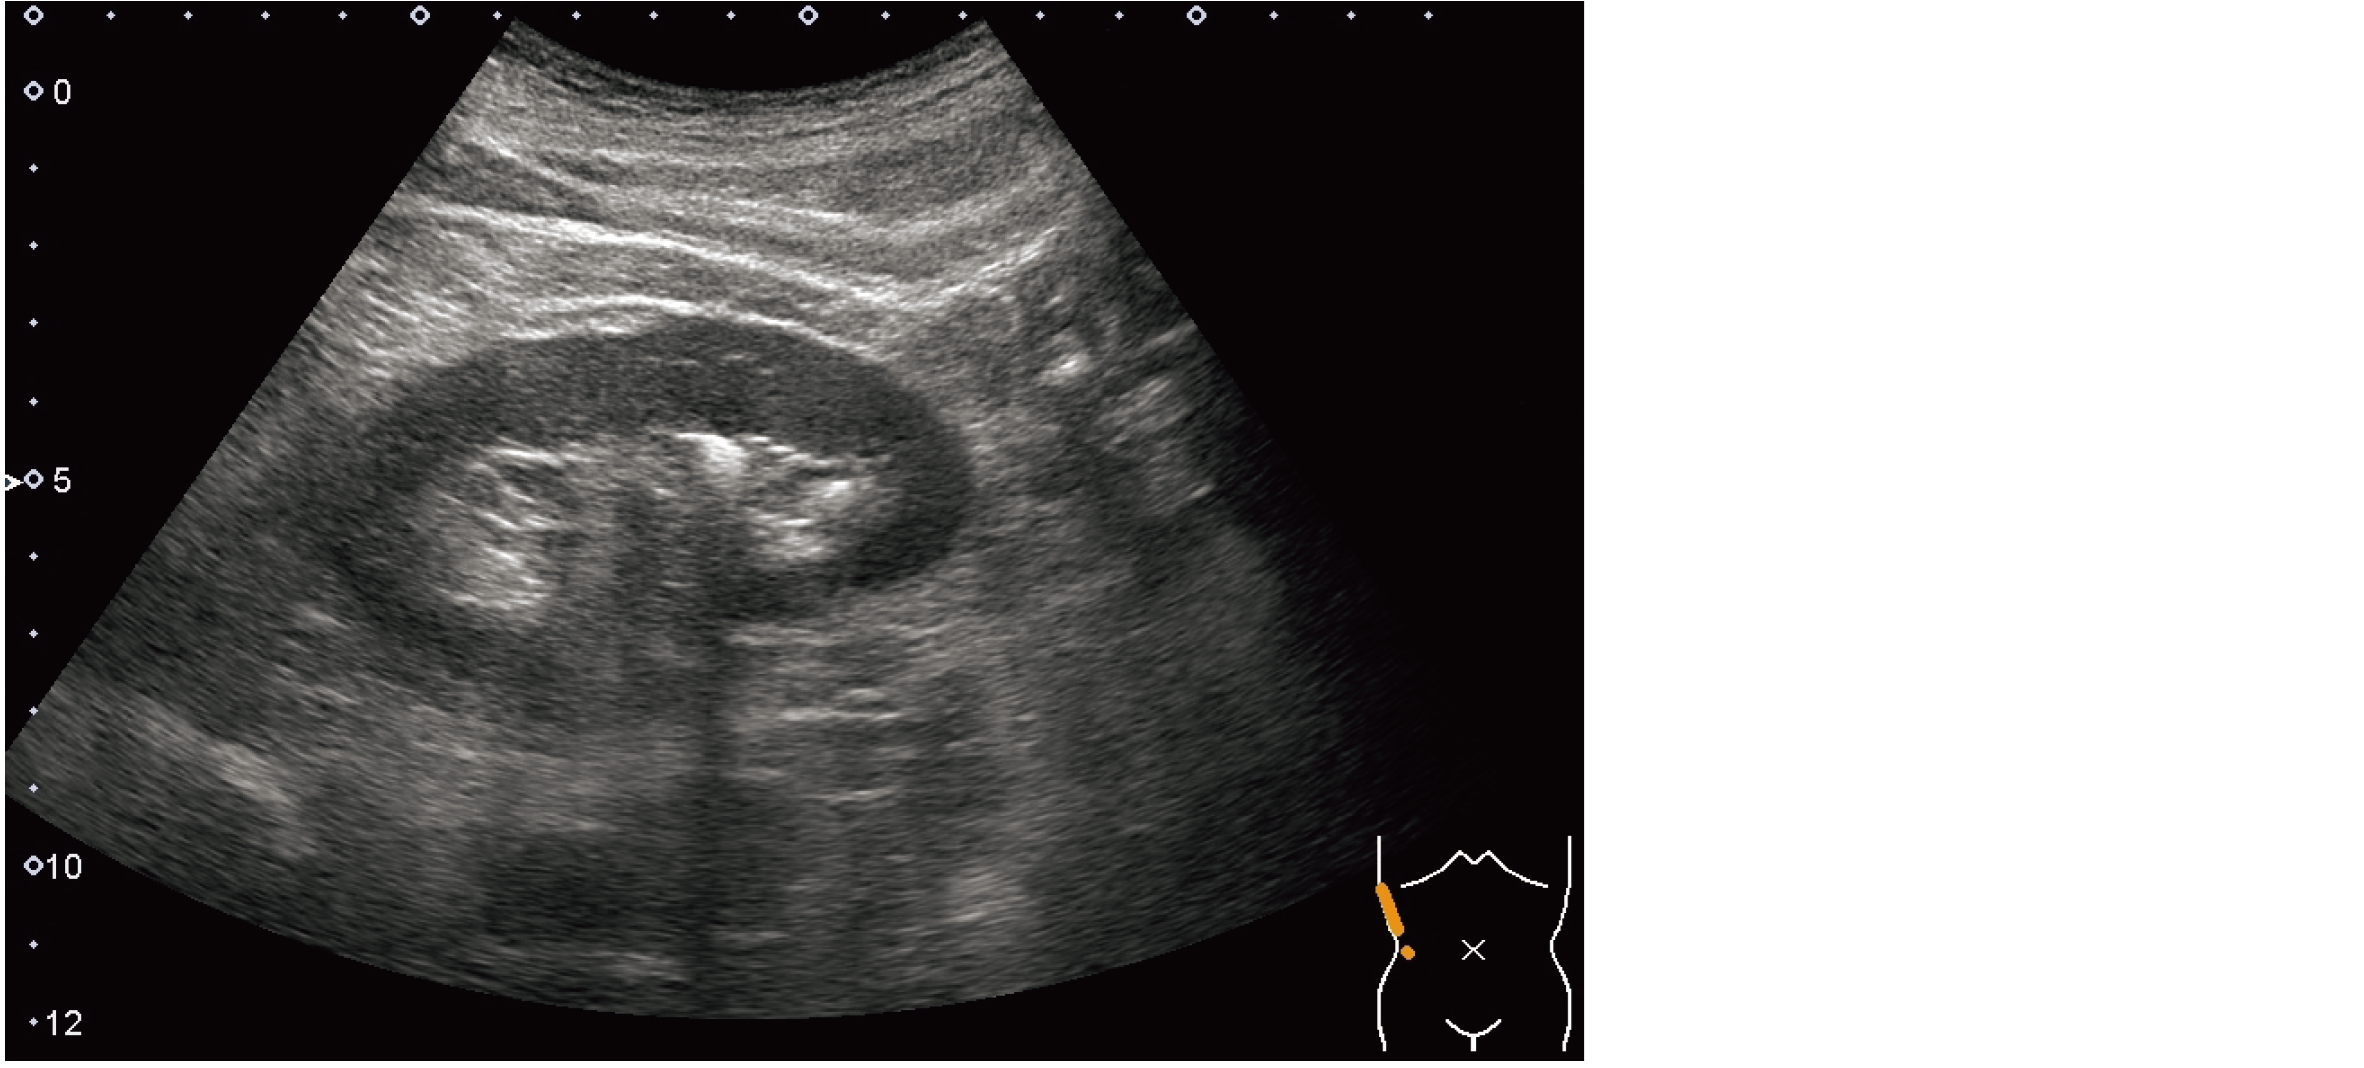

臨床生理学

(3.超音波・画像診断)

右側腹部超音波像を示す。

最も考えられるのはどれか。

1. 水腎症

2. 腎結石

3. 腎嚢胞

4. 尿管結石

5. 腎細胞癌